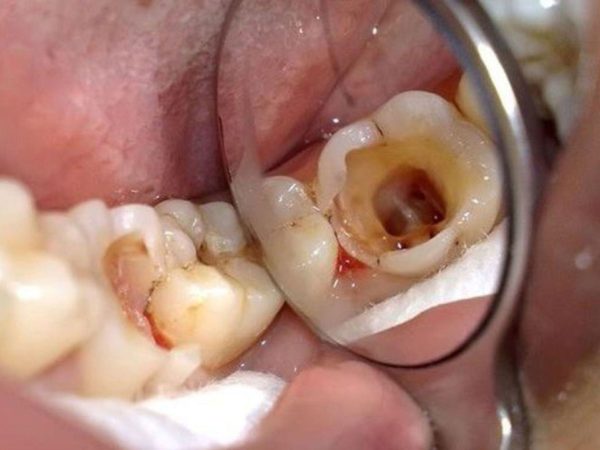

Sâu răng lan đến tủy, viêm tủy và chết tủy

Đây là tình huống phổ biến nhất cần điều trị nội nha trước khi phục hình. Khi sâu răng không được xử lý kịp thời, vi khuẩn sẽ ăn mòn men – ngà và xâm nhập vào buồng tủy, gây viêm tủy cấp hoặc mạn tính.

Biểu hiện thường thấy:

- Đau nhức dữ dội, đặc biệt về đêm hoặc khi ăn uống nóng – lạnh.

- Răng đổi màu xám sậm.

- Có thể xuất hiện sưng nướu hoặc áp xe quanh chóp răng.

Nếu không điều trị kịp thời, tủy sẽ chết (hoại tử), vi khuẩn lan rộng ra mô quanh răng, gây viêm xương ổ răng hoặc mất răng. Trong trường hợp này, lấy tủy là bước bắt buộc trước khi bọc sứ để loại bỏ hoàn toàn ổ viêm và bảo tồn phần thân răng còn lại.